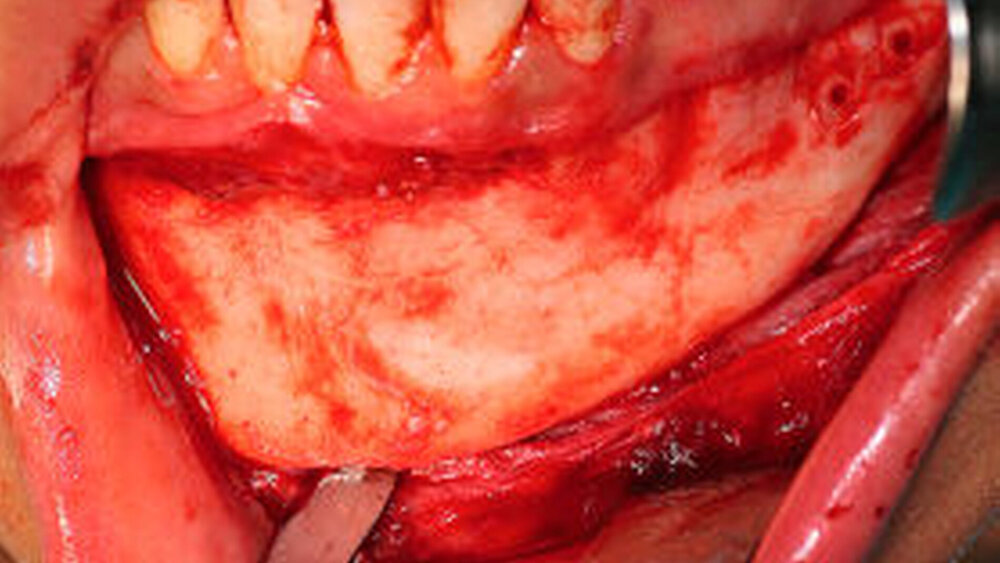

Anhand von CT-Daten wurde präoperativ individuell mittels CAD/CAM-Technik ein alloplastisches Implantat für den Kinn- und den linken Unterkieferbereich angefertigt (Abbildung 2). Nach Entfernung des Osteosynthesematerials im Unterkiefer beidseits wurde das mandibuläre Defizit (Abbildung 3) durch das individuell angefertigte alloplastische Implantat ausgeglichen und mit Osteosyntheseschrauben fixiert (Abbildung 4). Intraoperativ bestätigte sich die Anomalie des linken N. alveolaris inferior, wobei das Foramen mentale nicht aufgefunden werden konnte.